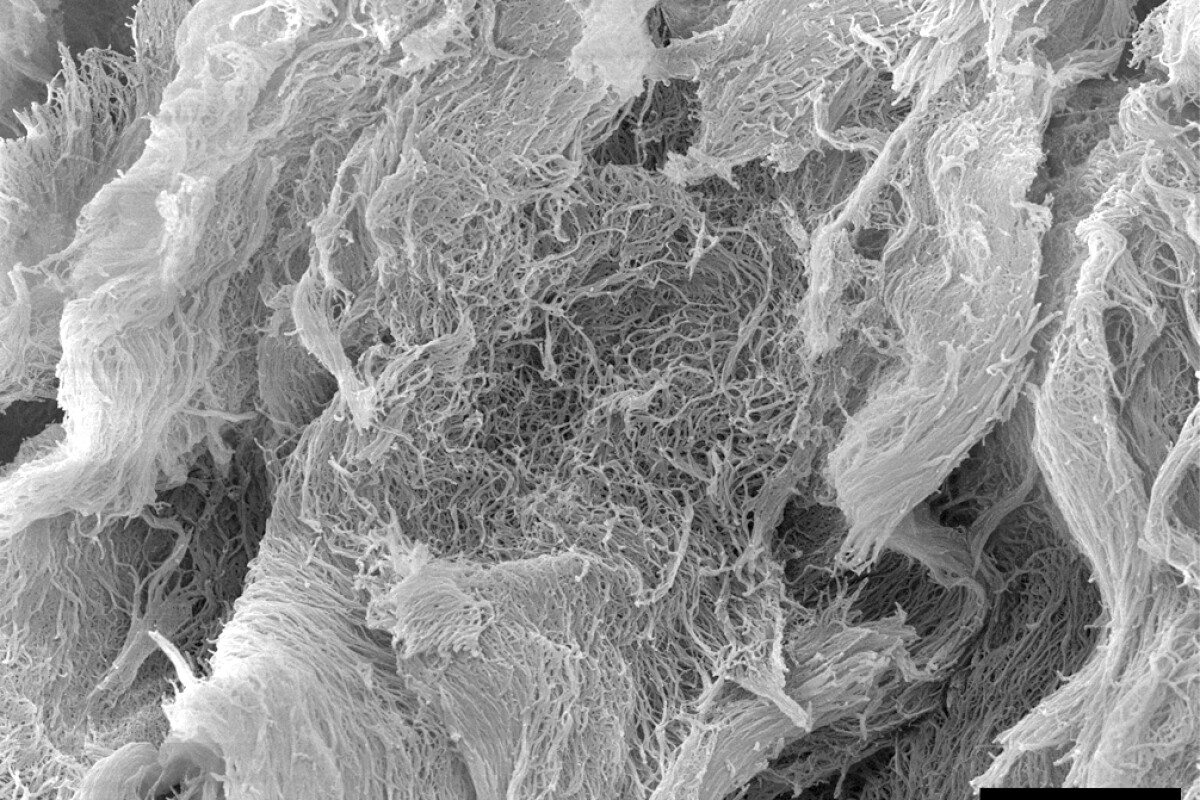

A scanning electron microscope image of the injectable cancer-fighting hydrogel, dubbed STINGel